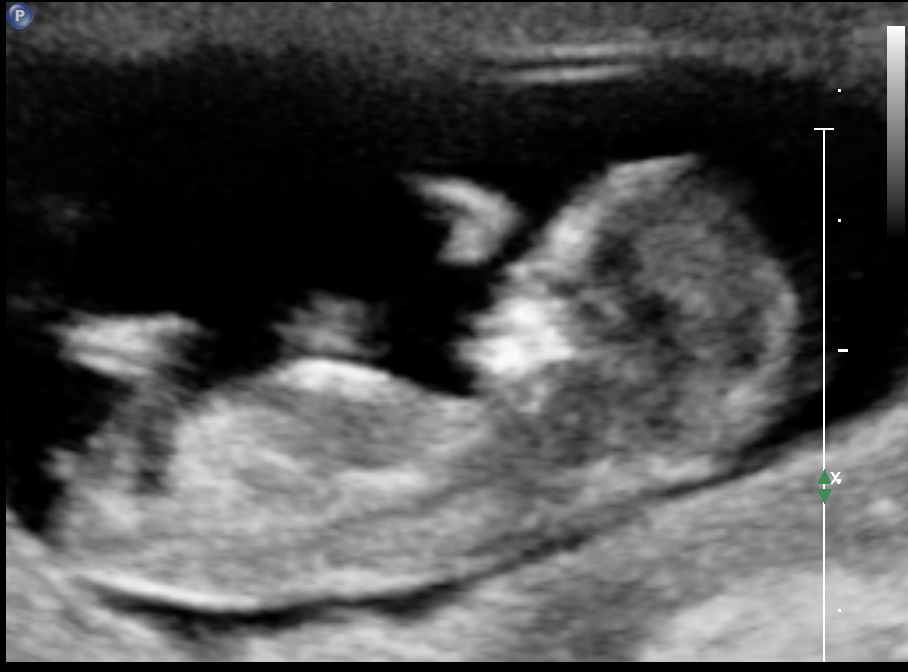

I'm new to this forum posting but I'm so curious if anyone has any guesses on what my lil bundle of joy is. So, what's everyone think- boy or girl? These were taken at my 12 week ultrasound.

What gestation based on O/LMP and what were you measuring as? I think it's probably a girl, especially if you're closer to 13w. If closer to 12w, I'm less confident.

Looks girly for now.....but it is still early and could change.....but I will say 70/30 girl :) congrats!

Tentative girl guess, but I agree it's early and you never know what a nub might do in just a week xx

I looks very much like a girlie nub :)

A slight girl lean. But still early.